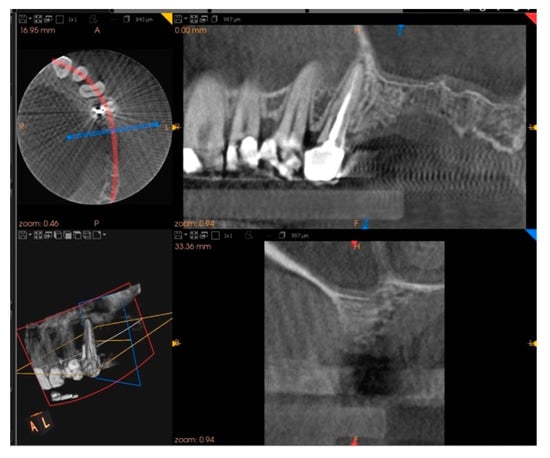

Five months after the extraction, a cone-beam computed tomography (CBCT) was also performed to design the implant insertion. The radiological examination showed bone volume preservation of the post-extraction site and no signs of osteonecrosis (Figure 9 and Figure 10).

Figure 9.

Cone-beam computed tomography (CBCT) shows bone volume preservation in the mesial surface of the alveolus.

Figure 10.

Cone-beam computed tomography (CBCT) shows bone volume preservation in the distal surface of the alveolus.